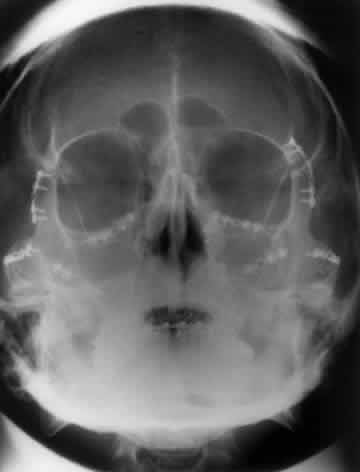

Because the orbit is in such close proximity to the larger bones of the skull, multiple shadows overlap one another and obscure some radiographic details. Numerous radiologic projections have been developed to evaluate the bony structures of the orbit and face.5,6 These various projections attempt to eliminate some of the obvious overlapping shadows and allow for better detail of the bony orbit. For maximal image clarity, the distance from the object to the x-ray cassette should be minimized and the distance between the subject and the x-ray beam maximized. This principle is demonstrated in Figure 1.

Fig. 1. In any projection the image detail is maximized using the minimal distance from the subject and the x-ray cassette. A. Anterior to posterior projection demonstrating decreased clarity and definition of anterior structures. B. Posterior to anterior projection showing the improved clarity of the anterior structures, such as the orbital rim and frontal sinus.